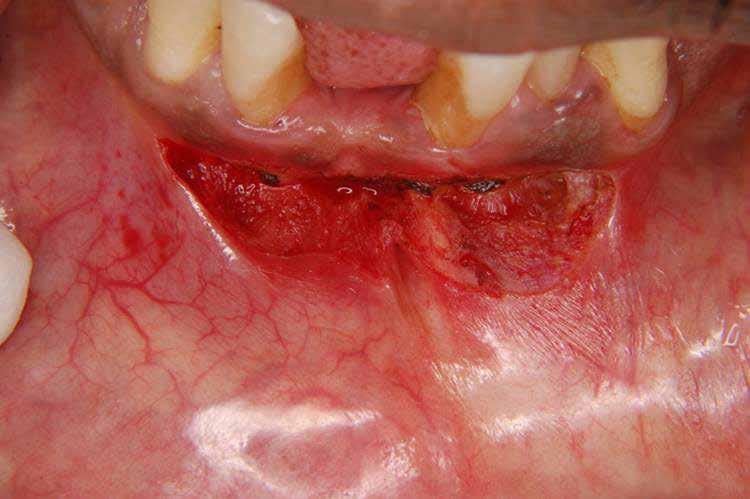

sok korrigálása, valamint az impaktálódott fog előtöréséhez szükséges hely megteremtését követően, egy merev acél ív segítségével stabilizáltuk a fogakat. Ezt követően elvégeztük a jobb felső nagymetszőfog sebészi feltárását. A fog koronáját csupán lágyrész borította, ezért nem volt szükség a csontállomány elvételére. A felszabadítás során egy 975

nm-es hullámhosszon pulzáló üzemmódban alkalmazott lézert használtunk (LaserHF standard, Hager & Werken). A teljesítménye 3 W, az aktív ciklus-idő 50%-os, a vezetőszál átmérője pedig 0,4 mm volt (2. ábra). A lézert 150 másodpercen keresztül alkalmaztuk. A fogat borító lágyrészek eltávolítását követően egy láncos brekettet rögzítettünk a metszőfog bukkális felszínére. A műtétet követően nem tapasztaltunk vérzést, nem alakult ki oedema, valamint a páciens sem számolt be fájdalom vagy bármely egyéb kellemetlenség fennállásáról. A felszabadítást követően a páciens minden hónapban háromszor jelent meg a felszabadított területre ránövő lágyrészek és az íny lézeres eltávolítása céljából. A beavatkozások során ugyanazt a lézer készüléket használtuk, mint amivel a felszabadítást végeztük. Közvetlenül a felszabadítást követően megkezdtük a fog finom extrudálását a láncos breketthez kötött füzérgumi segítségével.

2. ábra: Az impaktált fog lézerrel asszisztált sebészi feltárása. 3. ábra: A kezelés megkezdését követő 15. hónapban megfigyelhető a sikeres felszabadítást, fogmozgatást és pozicionálást követően látható állapot.